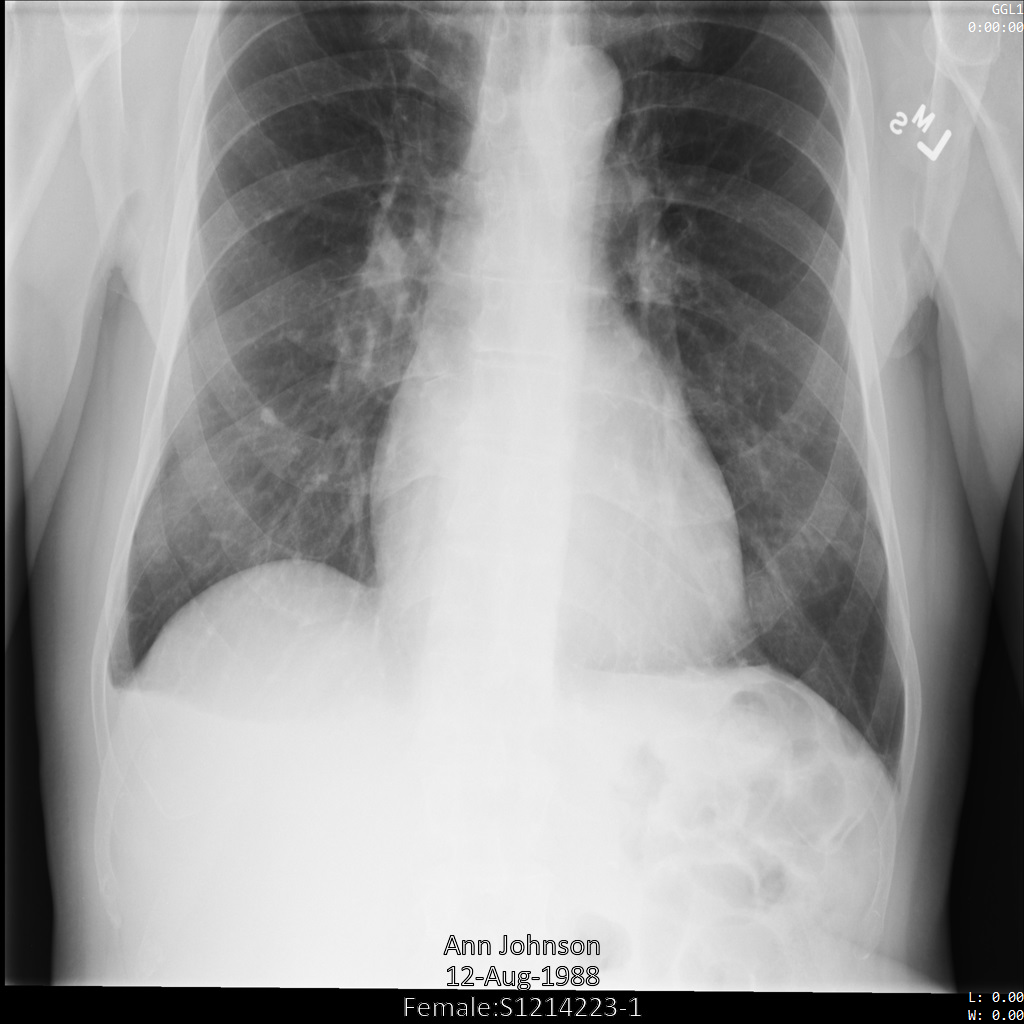

L'immagine seguente mostra una radiografia non oscurata di un paziente:

Dopo aver inviato l'immagine all'API Cloud Healthcare utilizzando

l'opzione REDACT_SENSITIVE_TEXT, l'immagine

viene visualizzata nel seguente modo:

Puoi notare che si è verificato quanto segue:

- Il

PERSON_NAMEin basso a sinistra dell'immagine è stato oscurato - Il

DATEin basso a sinistra dell'immagine è stato oscurato

Il sesso del paziente non è stato oscurato perché non è considerato testo sensibile secondo i tipi di informazioni DICOM predefiniti.